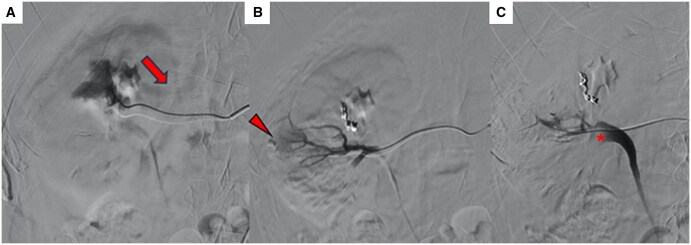

选择性栓塞是稳定患者外伤性肾假性动脉瘤(PSA)的首选治疗方法。n -丁基-2-氰基丙烯酸酯(NBCA)是一种常用的栓塞剂,用于栓塞周围病变。正丁基-2-氰基丙烯酸酯是应用最广泛的栓子材料之一,因为它易于制备,作用迅速,成本效益高。然而,在变得自信并能够安全地使用它之前,它的使用需要一个学习曲线。我们描述了一个病例的肾创伤性PSA栓塞没有明确的术前ct证据动脉-盏瘘,其中NBCA在肾盂的迁移发生在手术过程中。我们报告成功的多学科管理的并发症。

Selective embolization is the treatment of choice for traumatic renal pseudoaneurysm (PSA) in stable patients. N-Butyl-2-cyanoacrilate (NBCA) is an embolic agent frequently used to embolize peripheral lesions. N-Butyl-2-cyanoacrilate is one of the most widely used embolic materials because it is easy to prepare, it acts quickly and is highly cost-effective. Its use, however, requires a learning curve before becoming confident and being able to handle it safely. We describe a case of embolization of a renal traumatic PSA without clear pre-procedural CT-evidence of artero-calyx fistula in which the migration of NBCA in the renal pelvis occurred during the procedure. We report the successful multidisciplinary management of this complication.